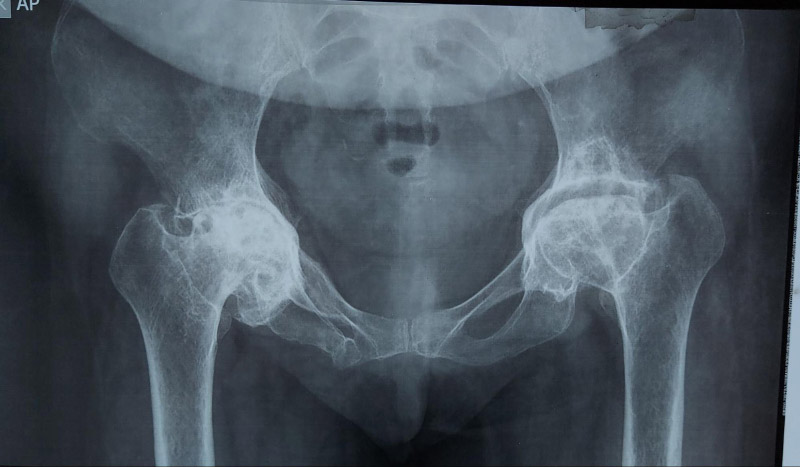

Cấp độ 4 – Nghiêm trọng: Khe khớp biến mất hoàn toàn, xuất hiện gai xương lớn, biến dạng nghiêm trọng tại đầu xương đùi và ổ cối.

Viêm khớp nghiêm trọng ở cả hai bên, hoại tử vô mạch khớp hông.Viêm khớp háng nặng ở cả hai bên.